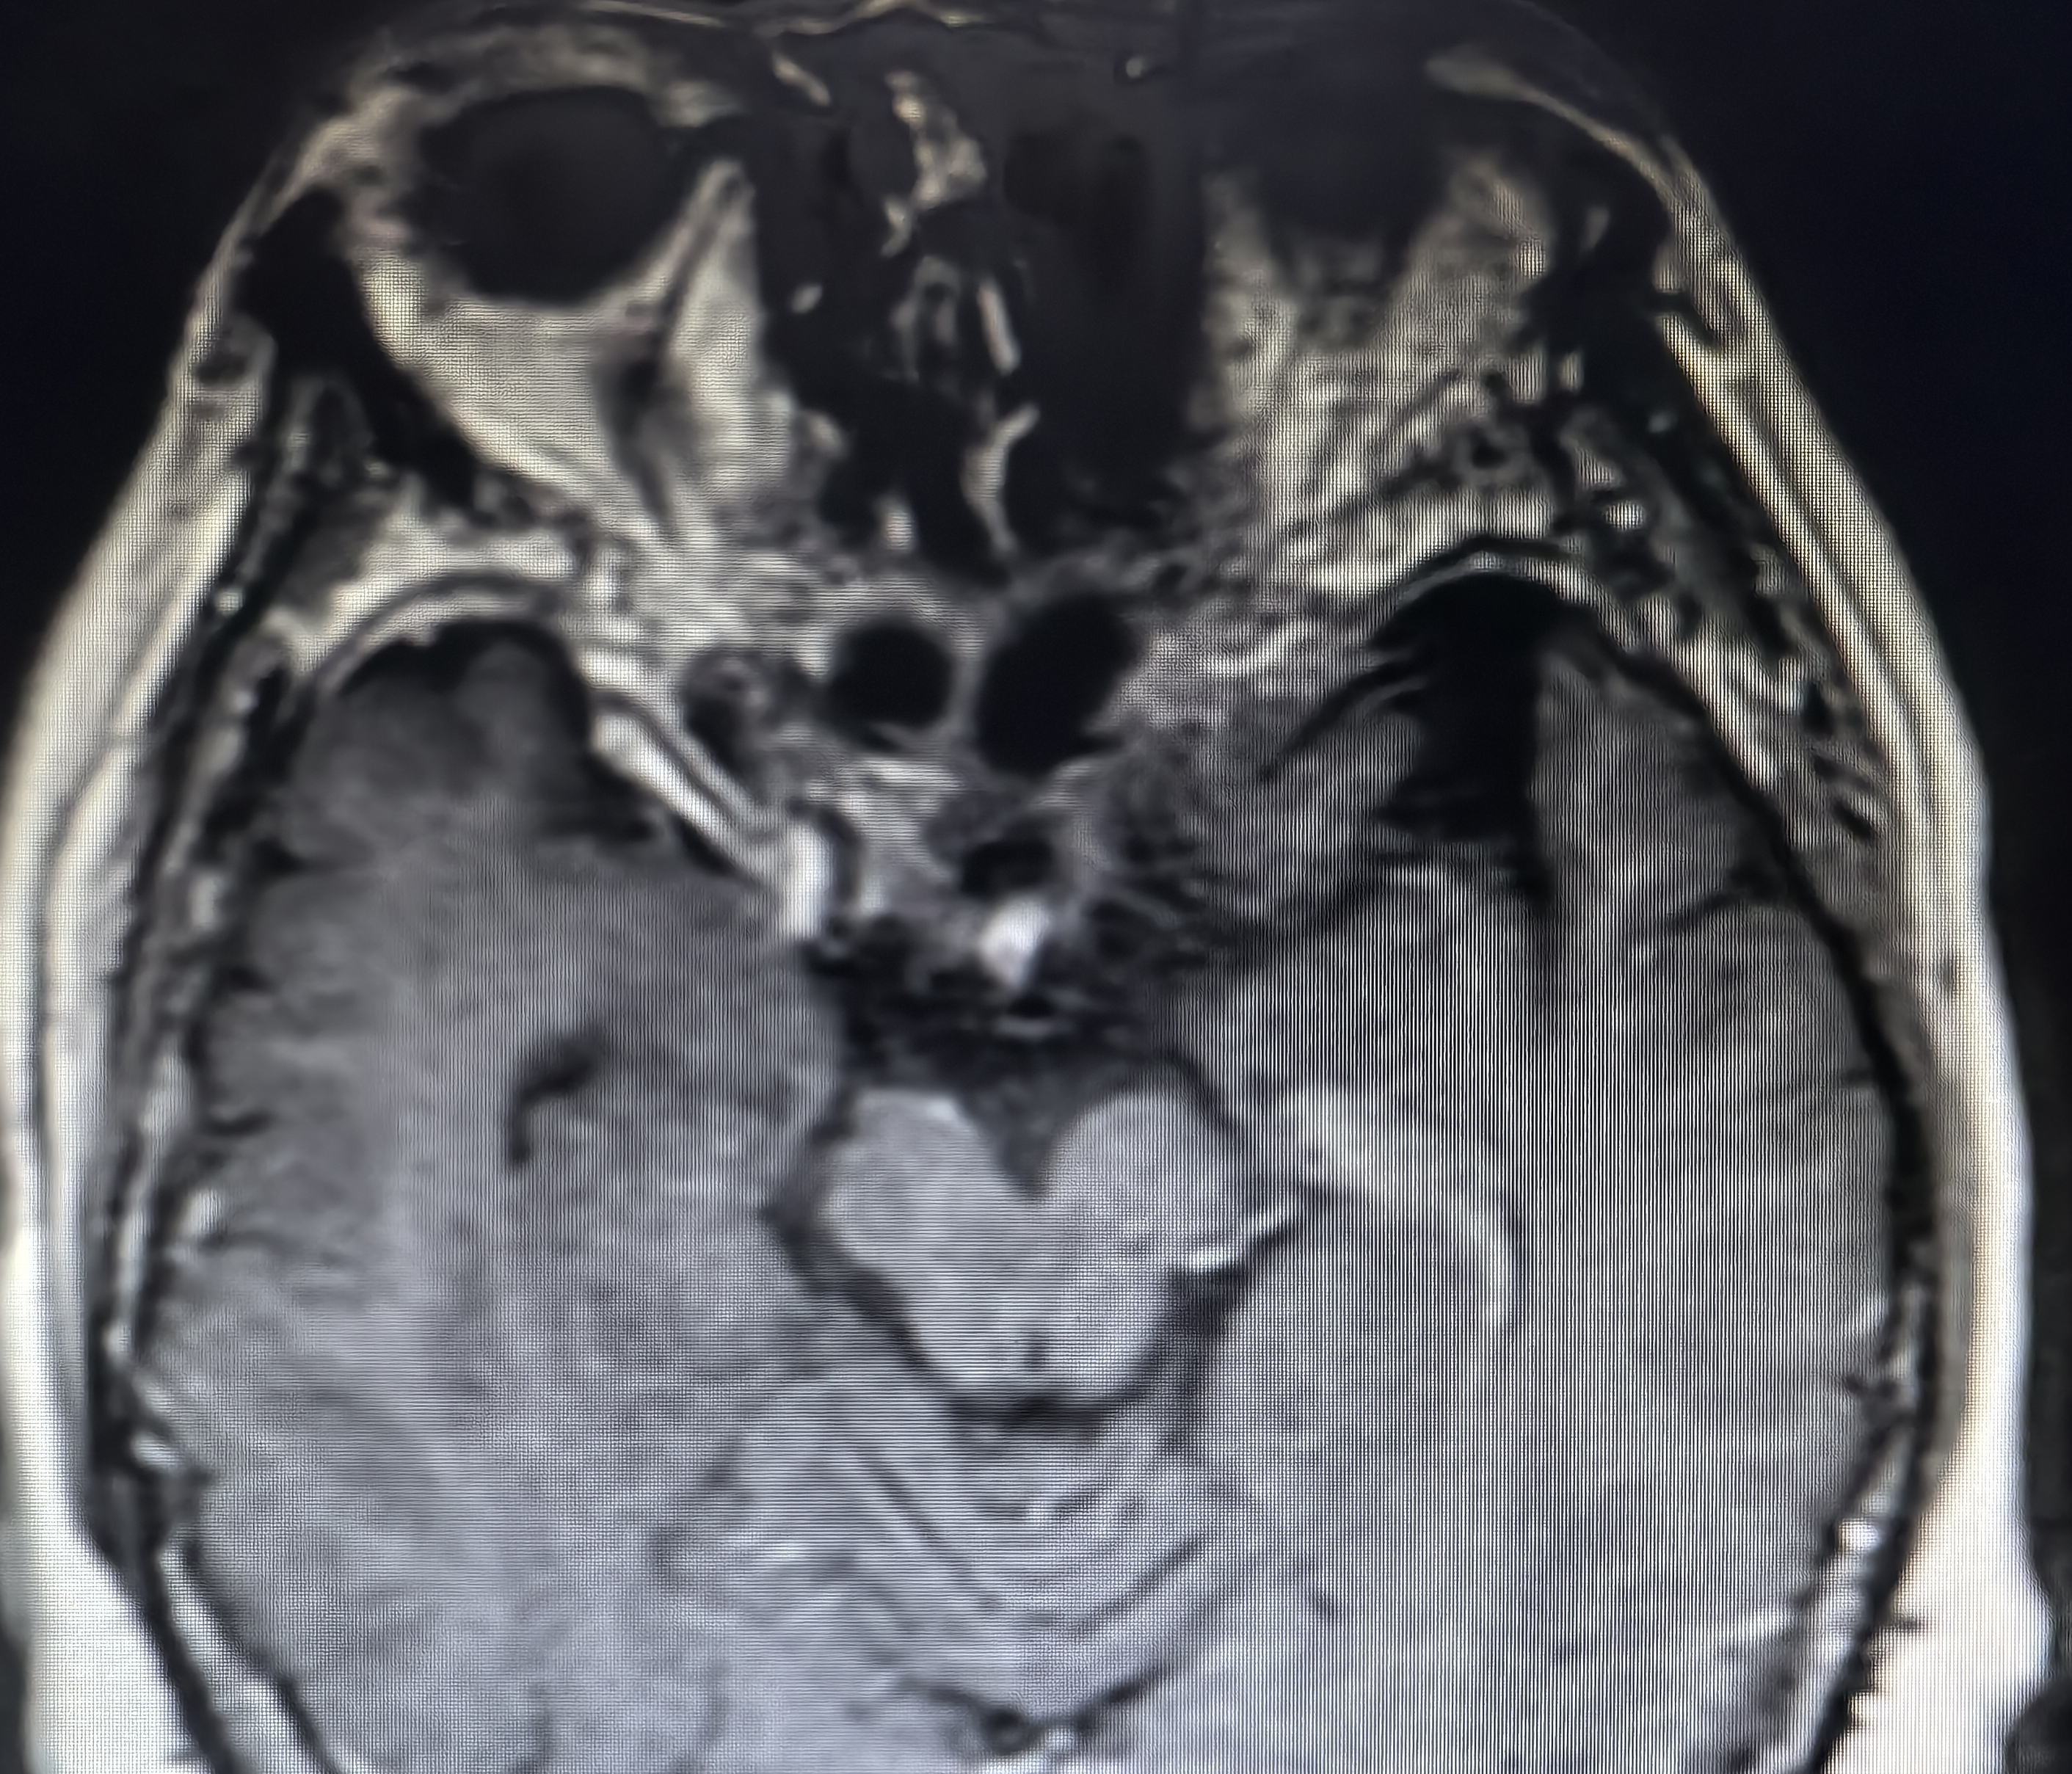

下面展示本病房几例病例:

病例二